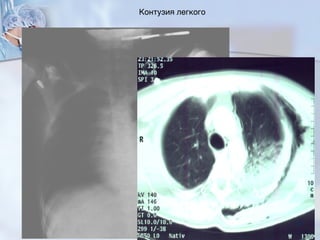

Контузия легкого

Часто при травме грудной клетки

контузия легкого без дыхательной недостаточности

Контузия легкого с дыхательной недостаточностью

▪ диспноя нет

▪ внешнее дыхание в норме

▪ малое затемнение легочной ткани

▪ полное затемнение; позднее тотальное затемнение

▪ диспное

▪ внешнее дыхание страдает 44

45

24-48 после травмы

Дефицит медиаторов

сурфактанта

Альтерация альвеолокапилярной

диффузии

дефицит насыщения газами крови

Увеличение объема поражения легкого 46

…увеличение до:

ARDS = белое

облочко=шоковое облочко

Терапия :

Ранняя интубация

Длительн.ИВЛ

Поза Фовлера

физиотерапия

Аккуратное инфузионная терапия

приводит!!